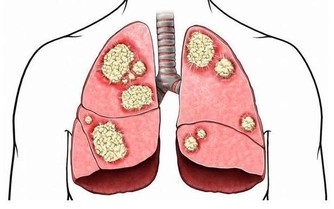

6、 遺傳因素也是一方面,痛風是一種遺傳代謝性疾病,具有遺傳性。患有痛風病的家族裡,如果不調節自己的飲食習慣,就很容易患上痛風。因為體內缺少一種酶,就不能把蛋白質分解。最後結晶成小晶體堆積在關節內,誘發疾病。